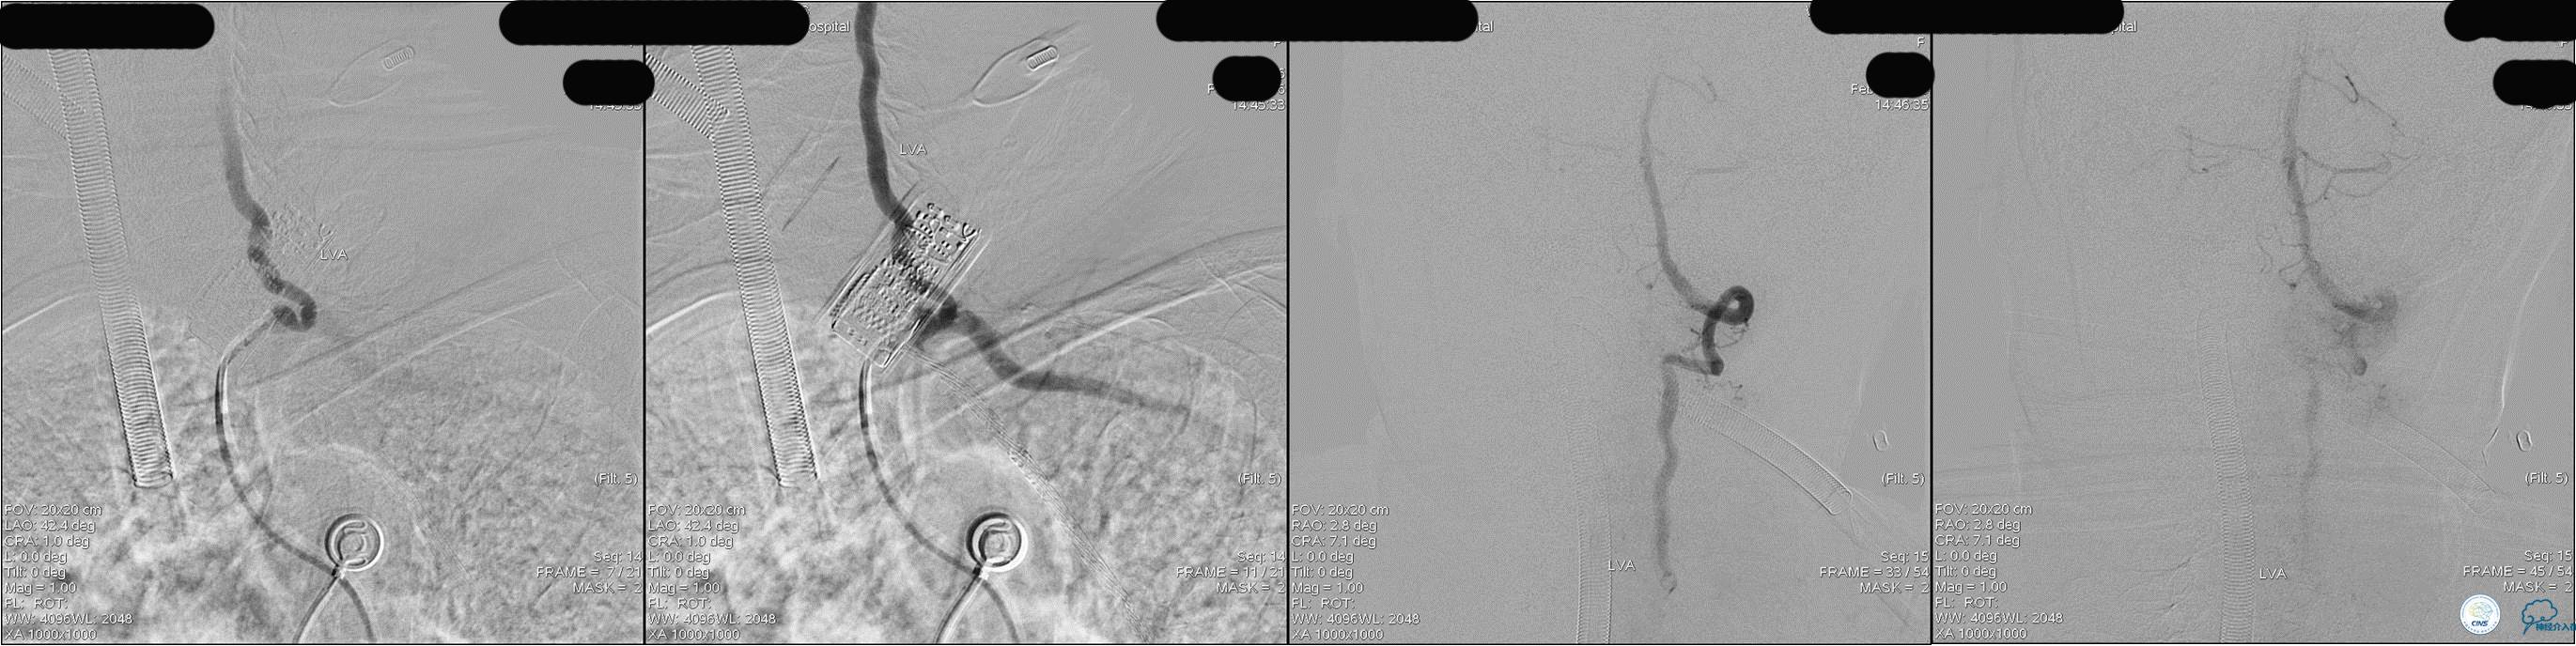

发病5.5小时给予股动脉穿刺

发现股动脉入路很差,考虑经桡穿刺。

》DSA资料(经桡动脉,5F导引导管)

》DSA资料(右侧椎动脉)

》DSA资料(前2次取栓,未取出,soli 4-20)

》DSA资料(第3次取栓)